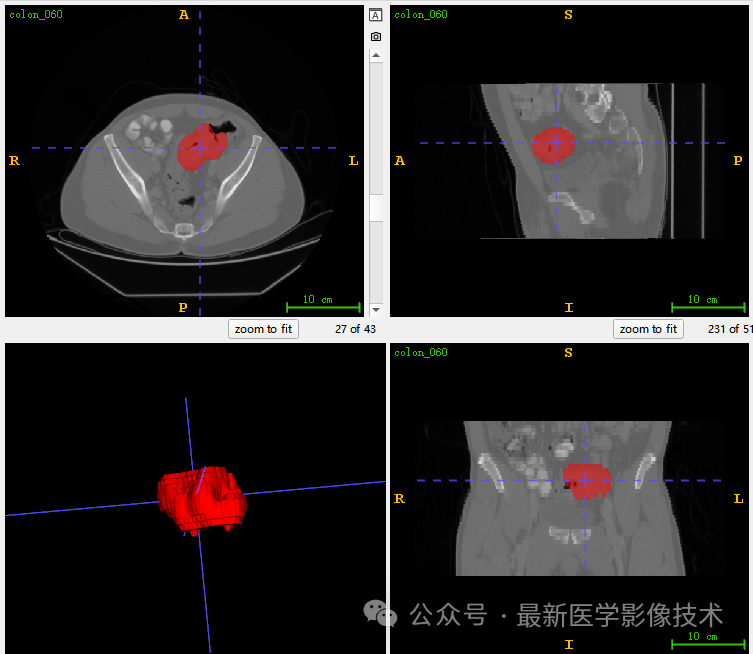

5、验证集分割结果

左图是金标准结果,右图是预测结果。